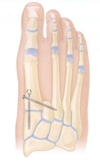

# Amputações - Dentro das amputações do pé, qual é a mais comum?

- Amputação de dedo

30

# Amputações - Dentro das amputações dos dedos do pé, qual é a mais comum?

- Amputação do 5° dedo

31

# Amputações - **V ou F:** - As amputações dos dedos do pé, de forma geral, conferem pouco morbidade, exceto a amputação do 2° dedo.

- Verdadeiro

32

# Amputações - Como deve ser realizada a amputação do 2° dedo do pé?

- A nível do 2° raio, incluindo o metatarso, mantendo apenas a base para evitar o desvio do 1° dedo

33

# Amputações - Porque é preferível optar pela amputação transmetatarsal nos casos de indicação de amputar 2 ou mais dedos do pé?

- Para conferir melhor função

34

# Amputações - Qual procedimento deve ser realizado para evitar equino nas amputações a nível da articulação de Lisfranc e Chopart?

- Reinserir o tibial anterior e o fibular curto e/ou enfraquecer o tendão de aquiles